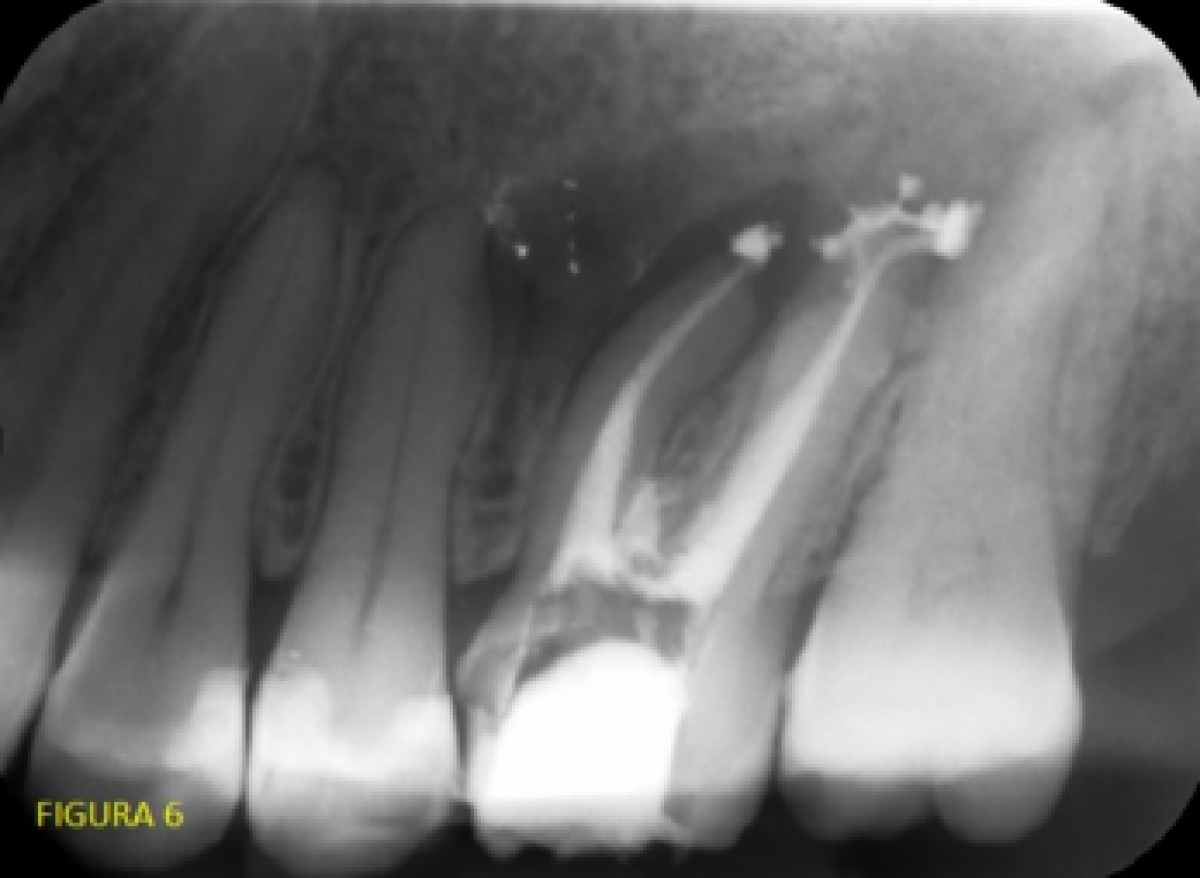

This meant we were able to retrace the canals in question and reach the apexes (even going a little beyond them with the cement). See end-of-treatment control X-ray (fig. 6).